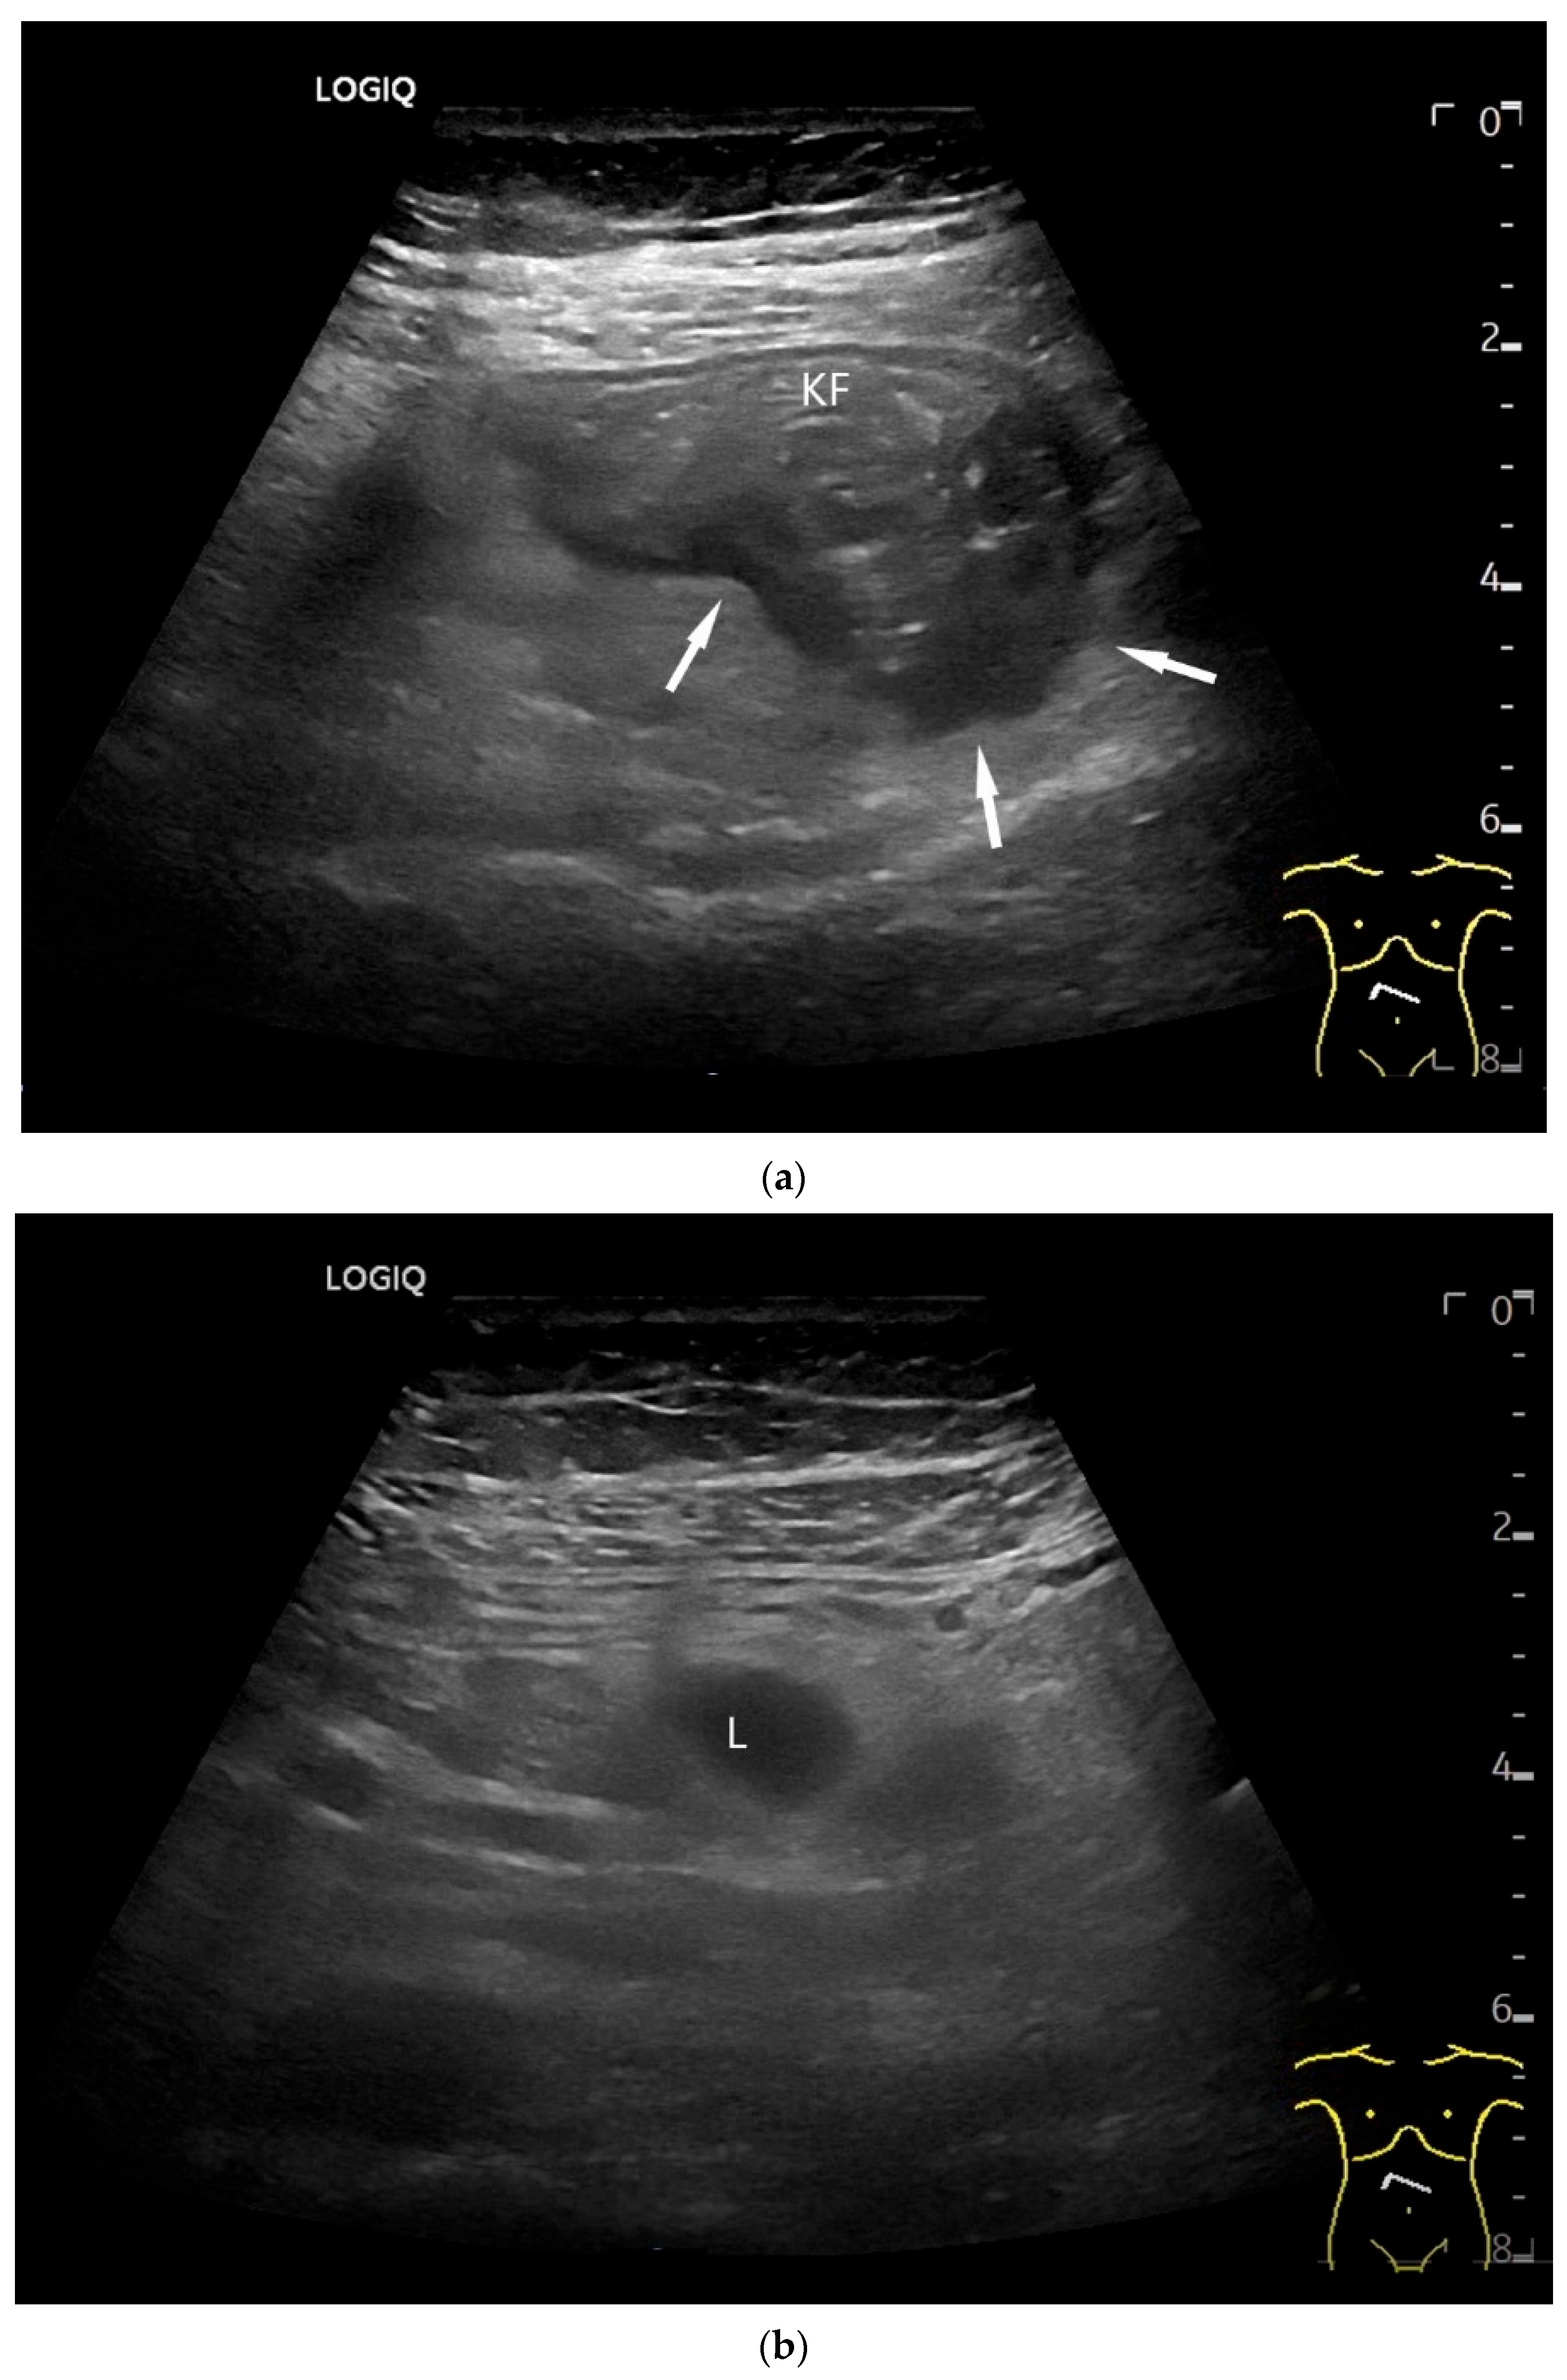

- Smereczyński, A.; Starzyńska, T.; Kołaczyk, K. Mesenteric changes in an ultrasound examination can facilitate the diagnosis of neuroendocrine tumors of the small intestine. J. Ultrason. 2015, 15, 274–282. [Google Scholar] [CrossRef]

| Neuroendocrine tumor | Small, nodular hypoechoic wall thickenings, mostly in the submucosa with spreading into the other layers. Usually with small vessels on CDI. Regionally enlarged lymph nodes. Multilocular manifestations are possible. |